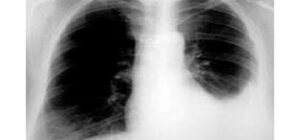

Tràn dịch màng phổi là gì?

Tràn dịch màng phổi là gì? Tràn dịch màng phổi ThS.BS. Nguyễn Hồng Đức Nguyên Trưởng khoa Phòng Khám – Bệnh viện Phạm Ngọc Thạch Cố vấn chuyên môn Trung tâm điều trị bệnh hô hấp Phổi Việt Mỗi lá phổi trong lồng ngực được bao quanh bởi 2 lớp màng rất mỏng gọi là […]